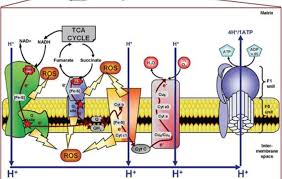

قیمت: 32٬000 تومان - دسته بندی فایل: پاورپوینتپاورپوینت زنجیره تنفس سلولی ، انتقال الکترون و فسفوریلاسیون اکسیداتیو

فروش ویژه پاوزپوینت حرفه ای زنجیره تنفس سلولی ، انتقال الکترون و فسفوریلاسیون اکسیداتیو با تخفیف استثنایی قیمت 24 هزار تومان تعداد اسلاید: 15 اسلاید